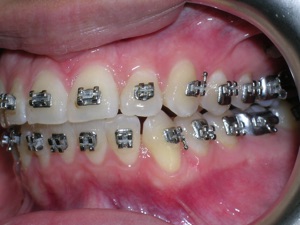

Here’s a case of crowding treated by trimming or narrowing of teeth. Also we utilized temporary anchor devices (mini screws) to help us keep the front teeth from sticking out too much.

Take a look at the braces applied as well as the trimming we did. Elastics were used from the mini screws.